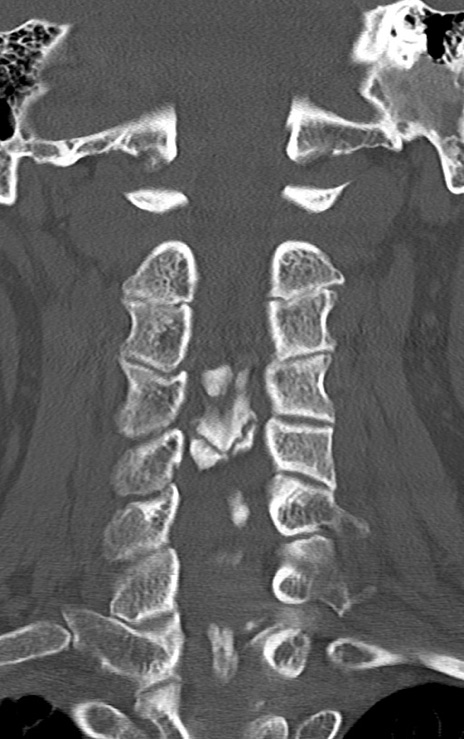

頚椎CT

矢状断像